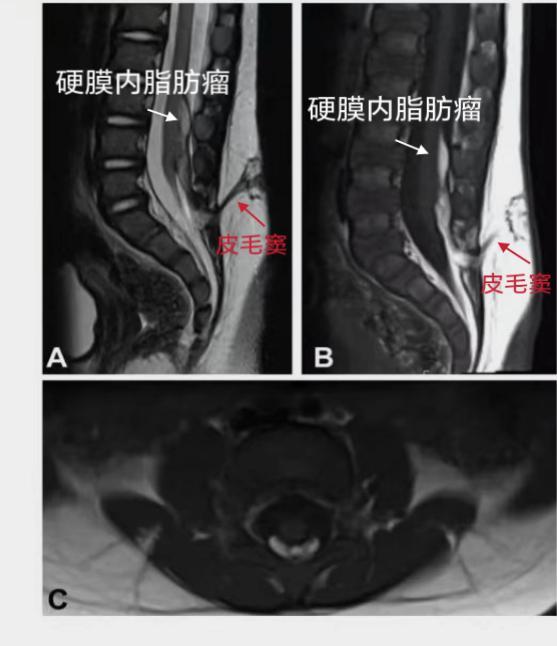

影像学检查是很有必要的,MRI是确诊脊髓栓系的首选方法和金标准,以下是MRI诊断脊髓栓系的几个要点:

3.其他相关改变:如椎管内外脂肪瘤、脊柱纵裂,脊髓空洞,椎体畸形以及腰骶部皮毛窦等等。